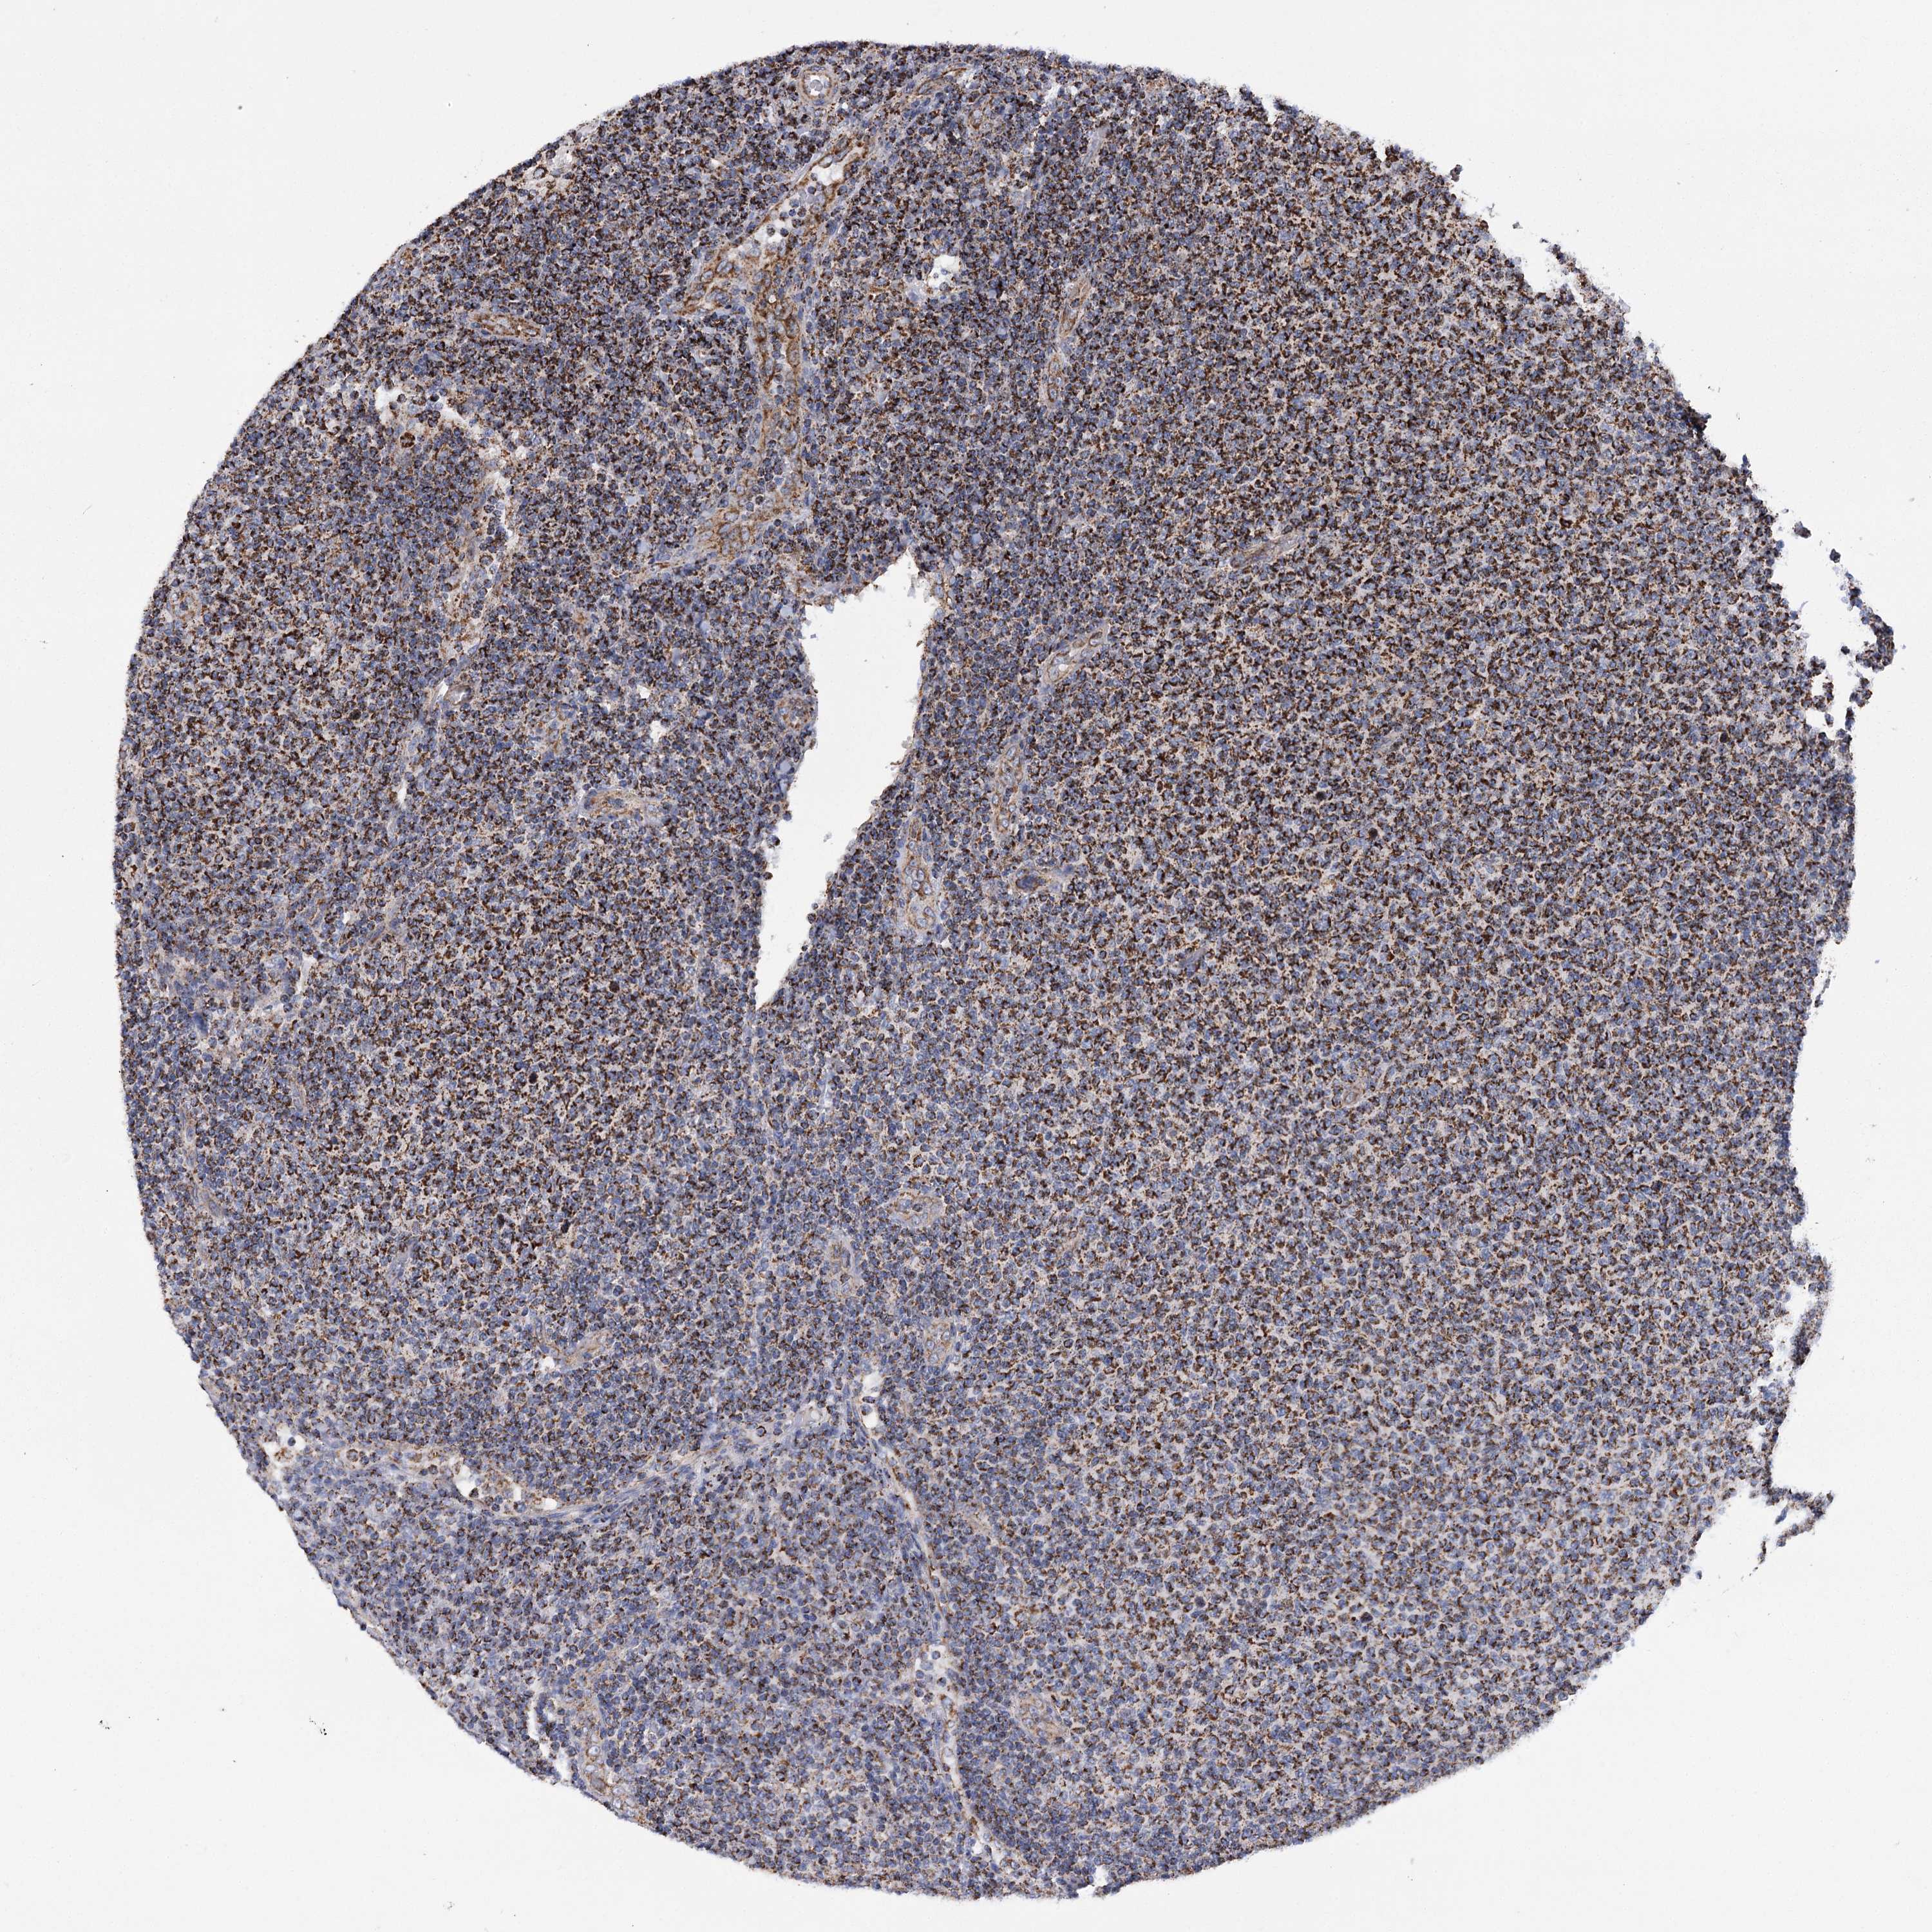

CANCER LYMPHOMA Show tissue menu

LYMPHOMA - Protein expressioni

A mouse-over function shows sample information and annotation data. Click on an image to view it in a full screen mode. Samples can be filtered based on level of antibody staining by selecting one or several of the following categories: high, medium, low and not detected. The assay and annotation is described here.

Each image is clickable and will lead to virtual microscopy that enables deeper exploration of all samples and also displays staining intensity scores, fraction scores and subcellular localization as well as patient and tissue information for each sample.

Antibody HPA038668

Antibody HPA038669

Hodgkin's disease, NOS

Malignant lymphoma, non-Hodgkin's type, High grade

Malignant lymphoma, non-Hodgkin's type, Low grade